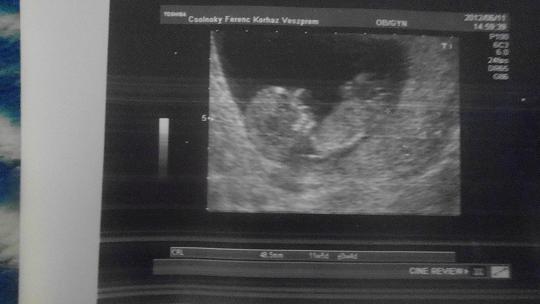

Mi hétfőn voltunk uh-n, Tomin nélkül (dolgozott)

, hát előtte éjjel rémálmaim voltak, reggel mondtam is neki, először megyek nélküled uh-ra, remélem nem hoz balszerencsét. Hál' Istennek minden a legnagyobb rendben, úgy tökéletes kistesó, ahogy van, 48,5 mm, napra pontosan megfelelnek a méretei (van olyan, ami nagyobb is), láttam a kezeit, lábait, köldökzsinórt, megszámoltuk az ujjait, nyaki redő, orrcsont rendben van, 1-2x mocorgott, de amúgy végigaludta az uh-t, az ujjai úgy álltak közben, hogy minden szuper

(hüvelykujja nyitva, többi csukva). Kaptam képet is, megvizsgált, levette a citológiát. Vérképem is szuper, jó a vasam, cukrom, vizeletem is.

Annyira furcsa, mert az álmosságon kívül minden rosszullétem elmúlt (előbb, mint Bencénél), folyamatosan eszem, úgyhogy az uh-n gördült le a kő a szívemről, hogy jól van, szépen nő a Pocaklakónk.

És a legújabb kép Pocaklakóról: